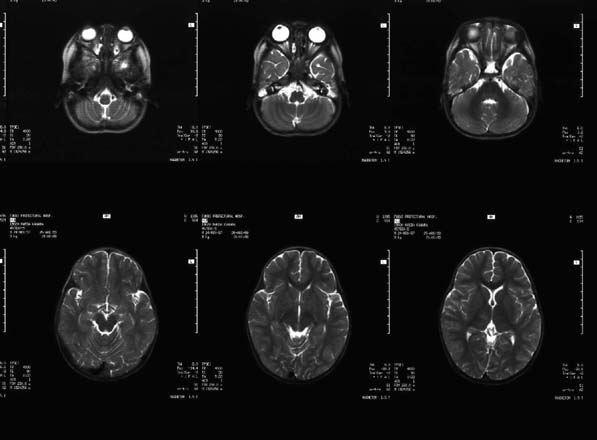

CaseHE02

- Age/Sex: 3 M

- Chief Complaint: けいれん発作重積状態

- Clinical Course:

- Lab. Data:

- Images:

- MR T1 (a)

- MR T1 (b)

- MR T2 (a)

- MR T2 (b)

- Tc-99m ECD Aug/27

- Tc-99m ECD Aug/31